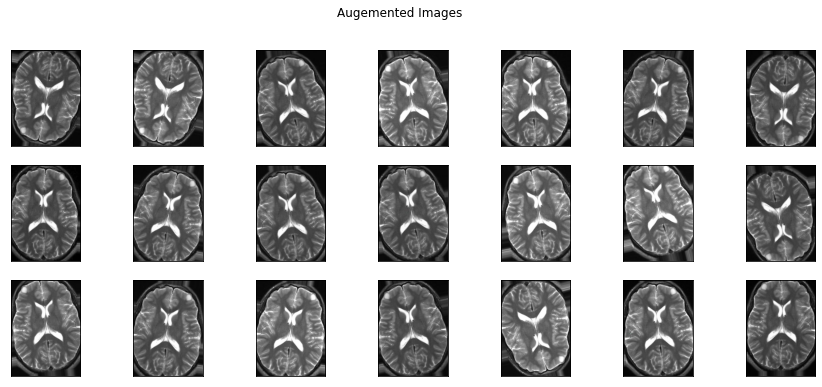

3) 데이터 증강 (Optional)

학습해야 할 이미지의 수가 부족하다면 개수를 증가(augmentation) 시켜야 해요! 사람이 보는 이미지와 컴퓨터가 인식하는 이미지는 약간의 차이가 있어요! 아래의 이미지를 보면 (flip, rotation, shear, crop)총 4가지의 방법으로 이미지를 지지고 볶고 해 두었는데요. 사람이 보았을 때는 전부 다 동일한 이미지지만, ‘0’과 ‘1’로 받아들이는 컴퓨터의 입장에서는 모두 다른 이미지로 인식해요!!